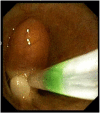

Figures